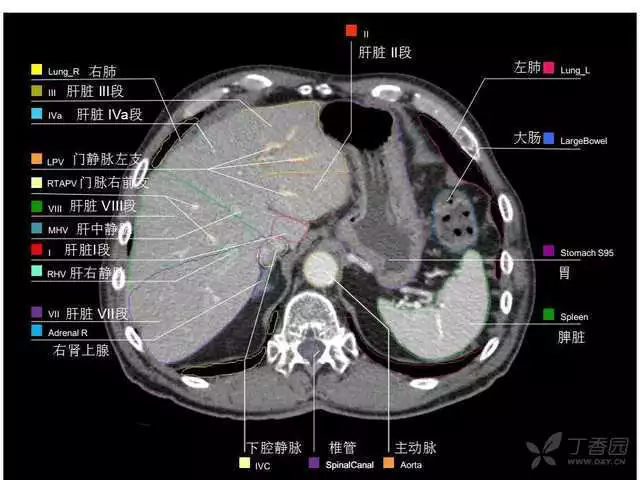

其实你离掌握上腹部 CT 影像只有一套高清实用图谱的距离,下面把我最喜欢的这本图谱分享给大家,为了方便阅读,我加了中文标识。后面附赠几张血管相对位置解剖关系图片,帮助大家理解(文中多图,建议在 wifi 环境下查看)。